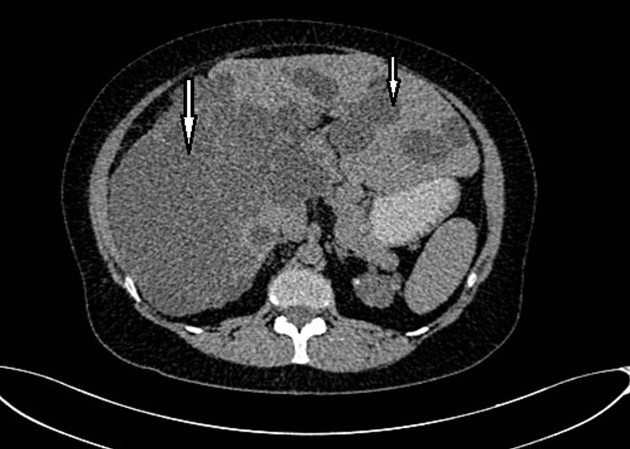

Abdominal tomography reported hepatomegaly secondary to polycystic disease and was reported with 3 cysts of greater size of 17, 14 and 12 cm in approximate diameter (Figure 1, Figure 2), kidney transplant without problems; the liver with mass effect on the stomach, the vena cava partially occluded, uncomplicated colon diverticulosis. Laboratory creatinine 1.44mg/dl urea 51.9 md/dl, glucose 71mg/dl, normal liver function tests.

Figure 1.Non-contrast CT shows hepatomegaly by multiple clusters of cysts.

Figure 2.Non-contrast CT shows multiple liver cysts with variable size and multiple renal cysts.